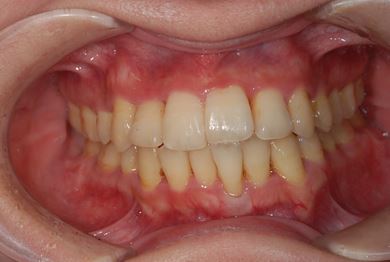

治療前

• 治療前